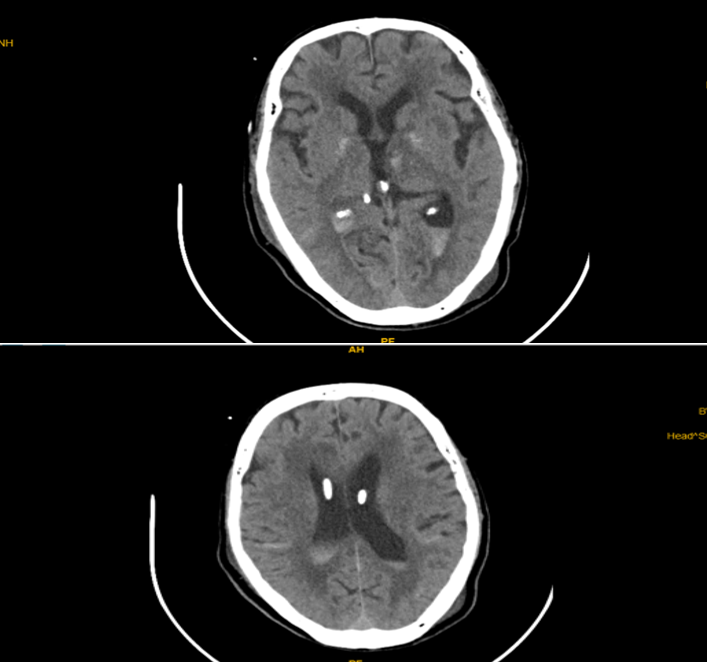

CT sọ não trước đặt EVD